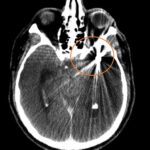

Fig. 2. TC de cerebro sin contraste post tratamiento: corte axial, evidenica artefacto metalico por material de embolización a nivel del valle Silviano izquierdo (circulo naranja).